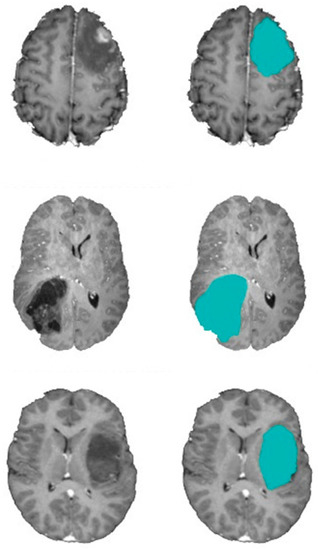

4. Experimental Results